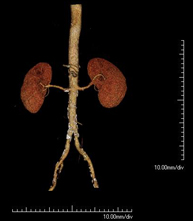

Prova diagnòstica no invasiva que consisteix en l'estudi de l'artèria aorta abdominal a través de l'obtenció d'imatges d'alta definició anatòmica mitjançant l'ús d'un equip de TC (Tomografia Computeritzada) i de contrast iodat. La qualitat de les imatges permet realitzar reconstruccions en 2D i 3D gràcies a estacions de treball especialitzades en l'estudi arterial. Està indicat en aquells pacients amb malaltia vascular (arteriosclerosi), en aneurismes d'aorta, en pacients amb dolor abdominal de possible origen vascular, en estudis prequirúrgics de lesions adjacents a l'aorta abdominal com a "mapa" vascular. La informació obtinguda de manera no invasiva és indispensable per als pacients que requereixen tractament percutani o quirúrgic. En aquells pacients que només requereixen seguiment de les lesions vasculars, aquesta tècnica és la tècnica no invasiva d'elecció juntament amb l'angio-RM. - Angio-TC Artèries renals

Prova diagnòstica no invasiva que consisteix en l'estudi de les artèries renals a través de l'obtenció d'imatges d'alta definició anatòmica mitjançant l'ús d'un equip de TC (Tomografia Computeritzada) i de contrast iodat. La qualitat de les imatges permet realitzar reconstruccions en 2D i 3D gràcies a estacions de treball especialitzades en l'estudi arterial. Està indicat en aquells pacients amb malaltia vascular (arteriosclerosi), en aneurismes d'aorta, en pacients amb dolor abdominal de possible origen vascular, en estudis prequirúrgics de lesions adjacents a l'aorta abdominal com a "mapa" vascular. La informació obtinguda de manera no invasiva és indispensable per als pacients que requereixen tractament percutani o quirúrgic. En aquells pacients que només requereixen seguiment de les lesions vasculars, aquesta tècnica és la tècnica no invasiva d'elecció juntament amb l'angio-RM. - Angio-TC Aorto-ilíac

Prova diagnòstica no invasiva que consisteix en l'estudi de les artèries ilíaques i l'aorta abdominal a través de l'obtenció d'imatges d'alta definició anatòmica mitjançant l'ús d'un equip de TC (Tomografia Computeritzada) i de contrast iodat. La qualitat de les imatges permet realitzar reconstruccions en 2D i 3D gràcies a estacions de treball especialitzades en l'estudi arterial. Aquesta prova està especialment indicada com estudi prequirúrgic (mapa vascular) abans d'intervencions percutànies o quirúrgiques d'aorta abdominal, com l'estudi complementari en pacients amb isquèmia de membres inferiors, etc. - Colonoscòpia virtual